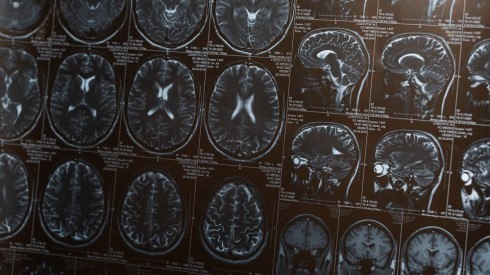

Привычка читать книги, писать и изучать иностранные языки может существенно снизить риск деменции в пожилом возрасте. К такому выводу пришли исследователи Медицинского центра Университета Раша в США, передает Tengri Life со ссылкой на Газету.Ru.